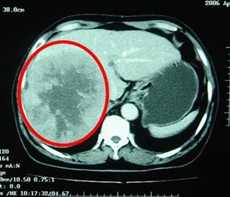

病例1 男,63歲,原發(fā)性肝癌晚期。AFP入院時為13000ng/L, 右肝區(qū)巨大腫瘤約為13×10=130 cm2。治療方案:介入栓塞一個月后肝動脈插管皮下置泵灌注今又生和5-FU。治療后:腹脹,腹痛消失,食欲增加,體重有所增加…